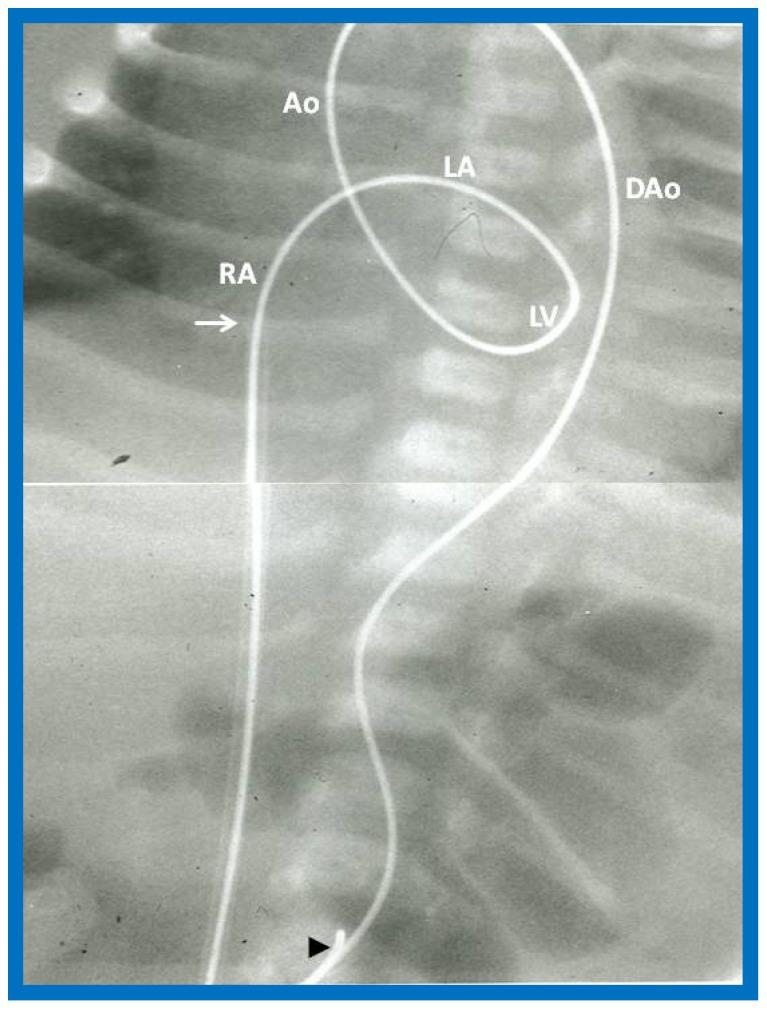

While investigating the outcomes of balloon dilatation procedures in patients with congenital obstructive lesions of the heart, several parallel observations were made. The purpose of this review is to present these observations/phenomena/innovations related to balloon dilatation of pulmonary stenosis (PS), aortic stenosis (AS), and aortic coarctation (AC). In subjects who had balloon pulmonary valvuloplasty (BPV), development of infundibular obstruction, electrocardiographic (ECG) changes, changes in right ventricular filling, role of balloon/annulus ratios on the results of BPV, and double balloon vs. single balloon BPV will be reviewed. In patients who had balloon aortic valvuloplasty (BAV), causes of aortic insufficiency and trans-umbilical venous approach for BAV are tackled. In children who had balloon angioplasty (BA) of AC, aortic remodeling and biophysical response after BA of AC are discussed.

在研究患有先天性心脏阻塞性病变患者的球囊扩张手术结果时,进行了几项平行观察。本综述的目的是介绍这些与肺动脉狭窄(PS)、主动脉狭窄(AS)和主动脉缩窄(AC)球囊扩张相关的观察结果/现象/创新。在接受球囊肺动脉瓣成形术(BPV)的受试者中,将对漏斗部梗阻的发展、心电图(ECG)变化、右心室充盈变化、球囊/瓣环比率对BPV结果的作用以及双球囊与单球囊BPV进行综述。在接受球囊主动脉瓣成形术(BAV)的患者中,探讨主动脉瓣关闭不全的原因以及BAV的经脐静脉途径。在接受AC球囊血管成形术(BA)的儿童中,讨论AC球囊血管成形术后的主动脉重塑和生物物理反应。